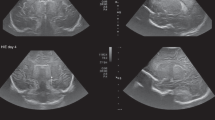

3D ultrasound

The 3D ultrasound modality provided information about the soft tissue and parts of the skull including the brain and ventricles, in different gray values (Fig. 1d). The skeletal information in 3D ultrasound images was very useful with respect to alignment and dimensional comparison of MRI and 3D ultrasound-derived ventricular models.